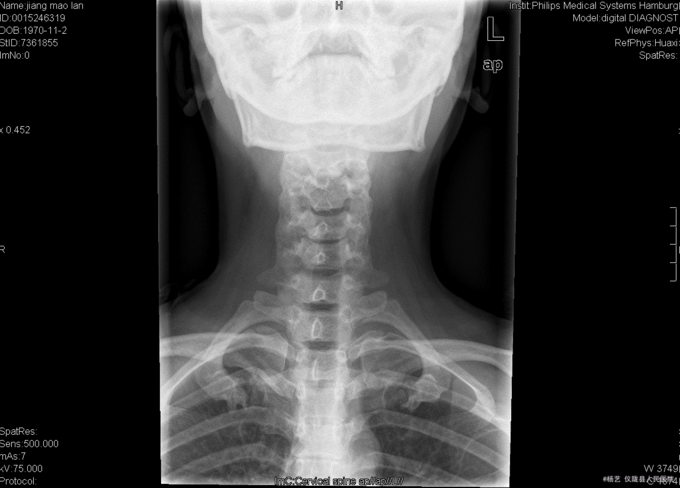

患者蒋茂兰,女,45岁0月,因“头晕伴视物旋转10+月,加重1+月。”入院 10+月前患者无明显诱因出现头晕、头昏;视物旋转,偶伴有呕吐,呕吐为胃内容物;间断发作,发作时持续时间不等,休息后明显缓解。无活动障碍;无肢体麻木、乏力;无行走不稳;无发热、头痛等,1+月前患者上述症状加重,患者于当地医院就诊,治疗未见明显好转。颈椎MRI示:颈5/6椎间盘突出。现患者为求进一步诊治就诊于我院,门诊以“C5/6椎间盘突出症伴脊髓神经不全损害”收入我科。

查体:T:36.9oC,P:78次/分,R:19次/分,BP:109/72mmHg。神志清楚,无病容,皮肤巩膜无黄染,全身浅表淋巴结未见肿大。。颈静脉正常。心界正常,心律齐,各瓣膜区未闻及杂音。胸廓未见异常,双肺叩诊呈清音,双肺呼吸音清,未闻及干湿啰音及胸膜摩擦音。腹部外形正常,全腹柔软,无压痛及反跳痛,腹部未触及包块,肝脏肋下未触及,脾脏肋下未触及,双肾未触及。双下肢无水肿。 专科查体:视:脊柱外观无畸形,活动无异常,无皮肤破溃及窦道形成。触:椎体棘上、椎旁肌无压痛、叩痛,四肢感觉无明显减退,远端血运未见异常。动量:颈部屈伸、左右侧偏活动无明显受限,双上肢耸肩、屈伸肘关节、屈伸腕肌力5级,双手握力5级,双下肢伸髋、屈髋、外展、内收、伸膝、屈膝肌力5级,双足趾背伸肌力5级。双侧肱二、三头肌肌腱反射、膝腱反射、跟腱反射正常引出。双侧Hoffmann氏征阳性,Babinski征阴性,踝阵挛阴性,髌阵挛阴性。 辅助检查:外院MRI示:颈椎退行性变,颈5/6椎间盘突出。垂体区:空泡蝶鞍?

综上初步诊断:1、颈5-6椎间盘突出症伴脊髓神经不全损害;2、白癜风 经前路颈5/6椎间盘切除、椎管及椎间孔减压、椎间融合器植骨融合内固定术。 手术发现:  颈5/6椎间隙变窄,椎间盘髓核干涩,无光泽。颈5/6椎间隙后份少量骨赘生成,椎间盘向后方突出,压迫硬脊膜。术中夹出数块突入椎管内的椎间盘髓核组织及增生骨赘。充分减压后,可见硬脊膜恢复膨隆,双侧神经根松弛,术中未见脑脊液漏。